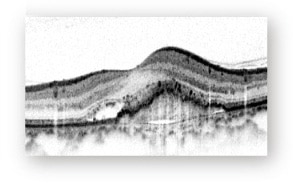

・光干渉断層計(OCT)

網膜は層構造になっており、その層構造を断面的に観察する検査です。

滲出や新生血管の状態がわかります。

<正常>

<滲出型加齢黄斑変性>